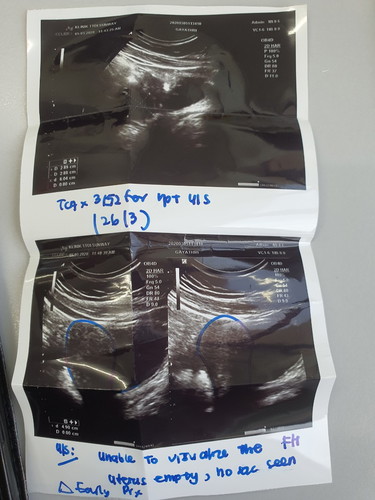

anyone experience light spotting and cramping during early pregnancy 4-6 weeks? normal ke? sy lewat period 15 Hari. upt negative. pegi scan ,doktor ckp early pregnancy. dlm 3 minggu kena scan lg sekali. By calculation 6 weeks. tapi dok scan Dan ckp baru mcm 4 weeks.